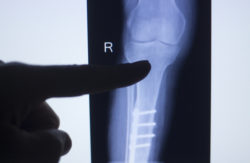

Radiolucent lines are one of the primary complications associated with Zimmer Persona tibial plate failure, which can be seen in X-ray images. These lines or gaps appear between the knee prosthetic and the bone, and is an early sign of device loosening.